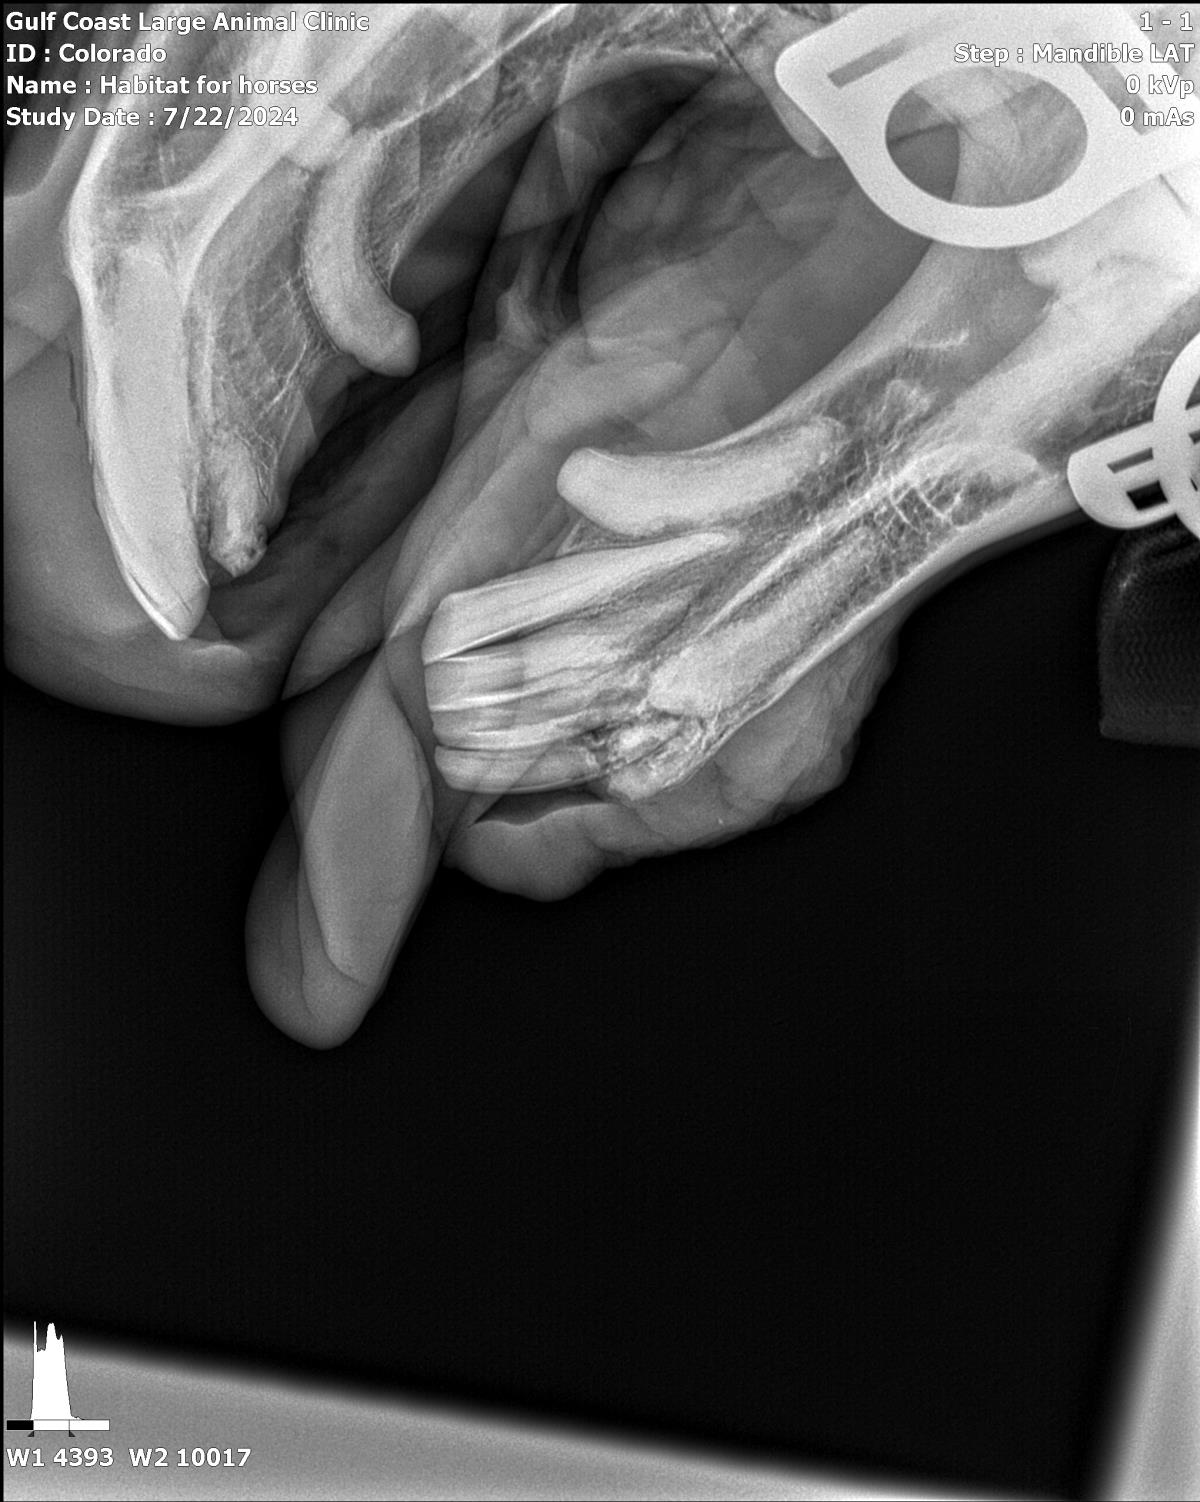

Pinto Colorado #21-010: Male Horse

Pinto Colorado

ID: 21-010 Horse

Breeds: Paint

Age: 22 years (approx.)